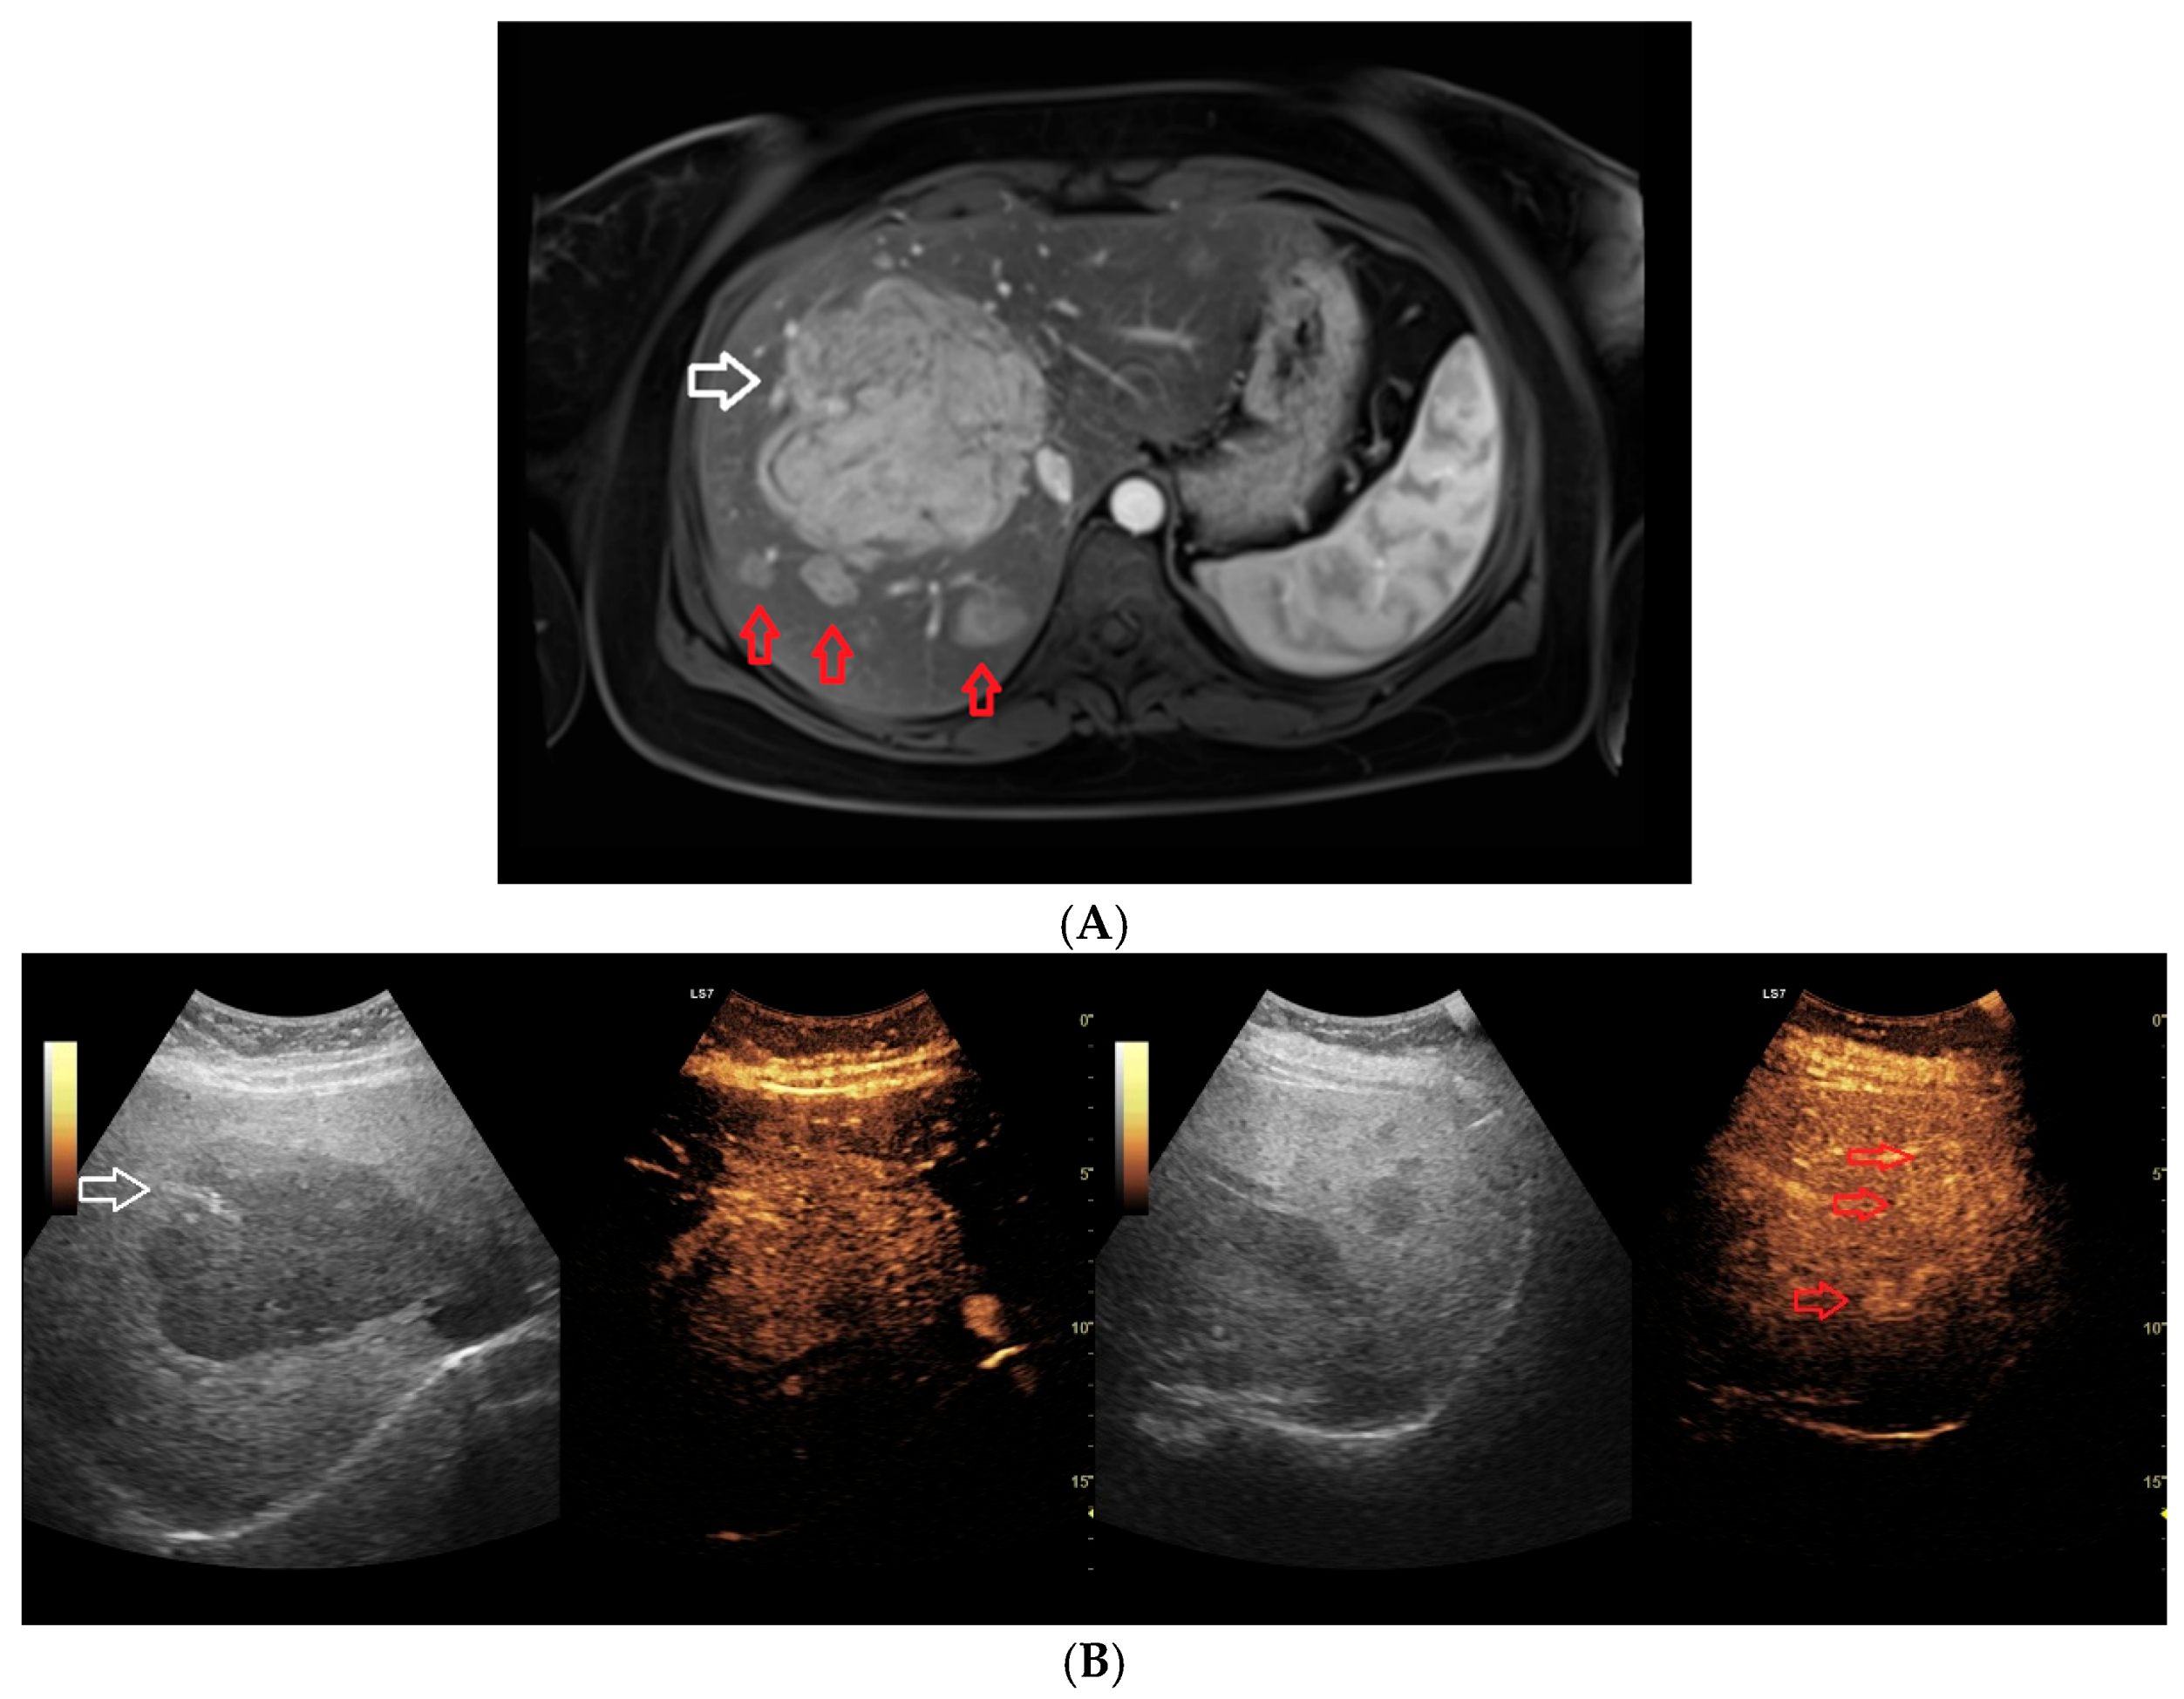

- Dobek, A.; Kobierecki, M.; Wieczorek, P.; Grząsiak, O.; Ciesielski, W.; Fabisiak, A.; Stefańczyk, L. Contrast-enhanced ultrasonography as a method of monitoring focal liver lesions—Initial report. Clin. Exp. Hepatol. 2024, 10, 120–128. [Google Scholar] [CrossRef] [PubMed]

- Dobek, A.; Kobierecki, M.; Ciesielski, W.; Grząsiak, O.; Fabisiak, A.; Stefańczyk, L. Usefulness of Contrast-Enhanced Ultrasound in the Differentiation between Hepatocellular Carcinoma and Benign Liver Lesions. Diagnostics 2023, 13, 2025. [Google Scholar] [CrossRef]